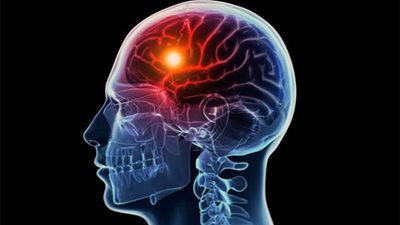

وزارة الصحة تتحدى السكتات الدماغية.. المرض يهدد 270 ألف ضحية سنويا.. جلطة المخ ثاني سبب للوفاة.. زيادة المستشفيات المعالجة.. توفير الأدوية وإنشاء وحدات رعاية مركزية

افتتح الدكتور أحمد عماد الدين راضي وزير الصحة والسكان، اليوم، مؤتمر الشرق الأوسط وشمال أفريقيا للسكتة الدماغية، الذي يعقد تحت رعايته على مدار يومين بمناسبة اليوم العالمي للسكتة الدماغية، بمشاركة عدد ...